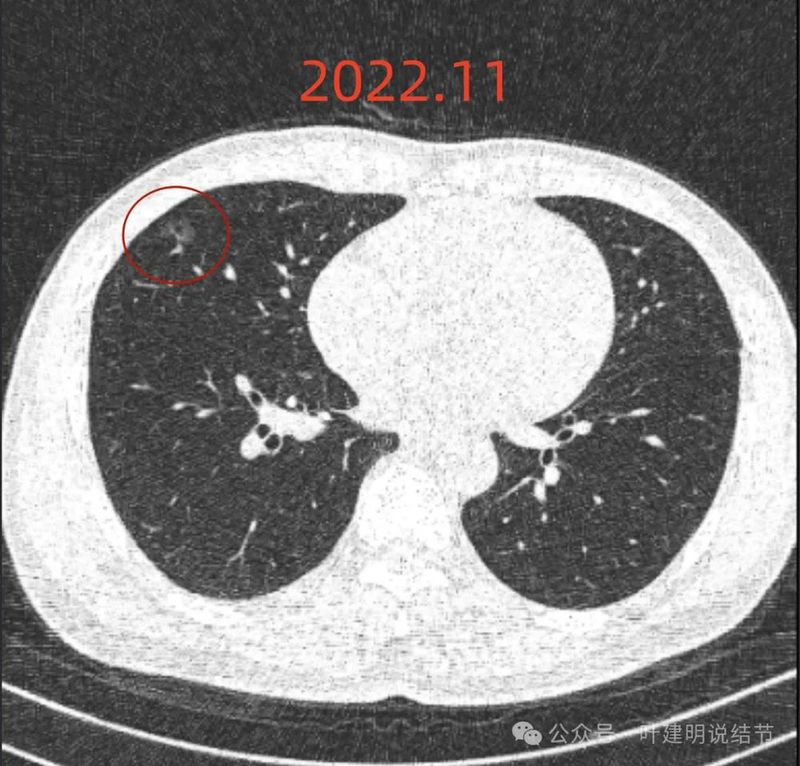

2022年11月时,病灶较前范围有所扩大,表面现分叶征,灶内有血管穿行,轮廓与边界清楚。